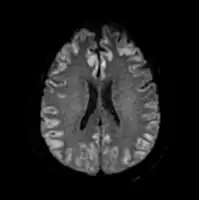

The diagnosis of hepatic encephalopathy is a clinical one, once other causes for confusion or coma have been excluded; no test fully diagnoses or excludes it. Serum ammonia levels are elevated in 90% of people, but not all hyperammonaemia (high ammonia levels in the blood) is associated with encephalopathy.[3][8] A CT scan of the brain usually shows no abnormality except in stage IV encephalopathy, when brain swelling (cerebral oedema) may be visible.[8] Other neuroimaging modalities, such as magnetic resonance imaging (MRI), are not currently regarded as useful, although they may show abnormalities.[14] Electroencephalography shows no clear abnormalities in stage 0, even if minimal HE is present; in stages I, II and III there are triphasic waves over the frontal lobes that oscillate at 5 Hz, and in stage IV there is slow delta wave activity.[3] However, the changes in EEG are not typical enough to be useful in distinguishing hepatic encephalopathy from other conditions.[14]